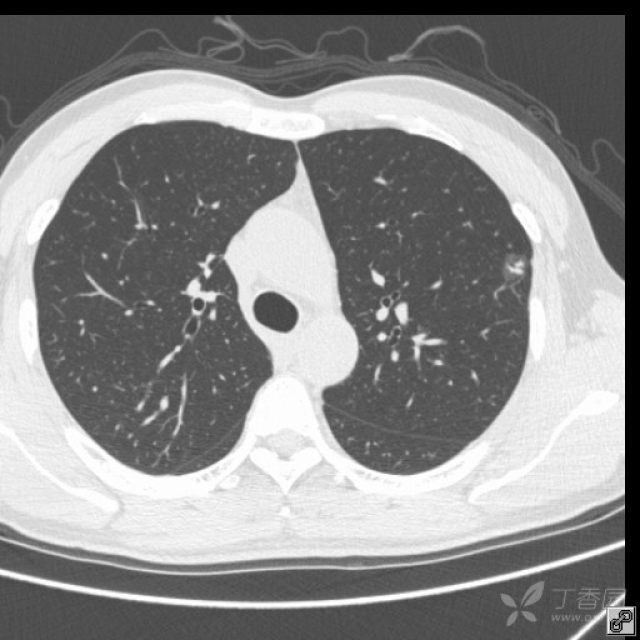

初次检出的部分实性或非实性结节性病灶-应对策略_肺部结节_肺部结节

肺部结节诊治要点